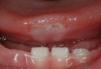

Physical ExaminationOn examination, the infant presented a round indurated ulcer that measured 1×1cm and had well-defined borders. The ulcer was situated on the ventral surface of the tongue, coincident with the lower incisor teeth (Fig. 1). A whitish exudate covered the base of the lesion, in which there were 2 deeper linear ulcers. There were no palpable cervical lymph nodes and no other skin or mucosal lesions. The child presented good height and weight gain and neurological examination was normal.

Clinical Course and TreatmentThe patient received dental treatment with smoothing of the edges of the incisor teeth. At 4 weeks the lesion had reduced in size (Fig. 2), and a month later it had completely disappeared.